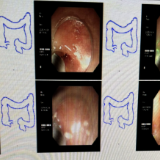

手术当天,刘跃辉熟练操作结肠镜顺利抵达阑尾内口,经过生理盐水反复冲洗阑尾腔后,彻底清除脓液;再通过网篮精准取出黄色结石及泥沙样结石,解除了阑尾腔的梗阻。整个手术过程顺利、高效快捷,术中无出血、无创伤。术后,晨晨的腹痛症状立即得到明显缓解。

内镜逆行阑尾炎治疗术(ERAT)是一项治疗急性非复杂性阑尾炎的新技术,与传统外科手术相比,ERAT技术具有简便、创伤小、无疤痕、起效迅速、恢复快等优势之外,还保留了阑尾免疫、分泌等生理功能,尤其适合具有保留器官意愿者、孕妇、儿童、青少年及不能耐受外科手术治疗患者。